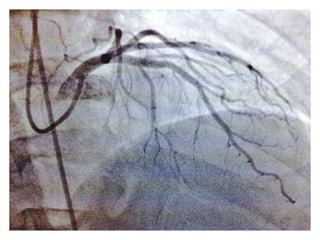

CASO CLINICO #3 MASCULINO 65 AÑOS DE EDAD DIABETES TIPO 2 DESDE HACE 15 AÑOS POBRE CONTROL METABOLICO DISLIPIDEMIA. OBESIDAD GRADO II. CUADRO CLINICO: ANGINA DE PECHO ATIPICA. CHEQUEO DE RUTINA. ECG DE REPOSO NORMAL. PRUEBA DE ESFUERZO POSITIVA Y PRECOZ PARA ISQUEMIA. TA 120/ 68 mm Hg. FC 67/min Fr 13/ min Glucosa en Ayunas 215 mg /dL. Colesterol total 260 mg/dL, LDL 135 mg d/L Creatinina 1.2 mg/dL EXAMEN FISICO ANODINO